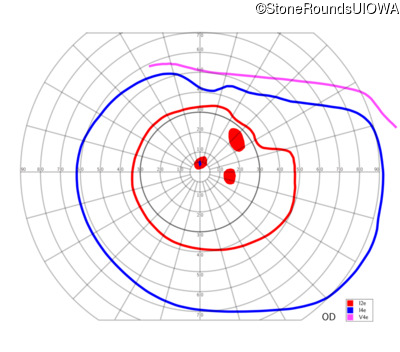

AR Stargardt Disease (IIA)

AR Stargardt Disease (IIA)

This 11 year old female first had difficulty seeing the blackboard at age 8. Later, she developed some photophobia.